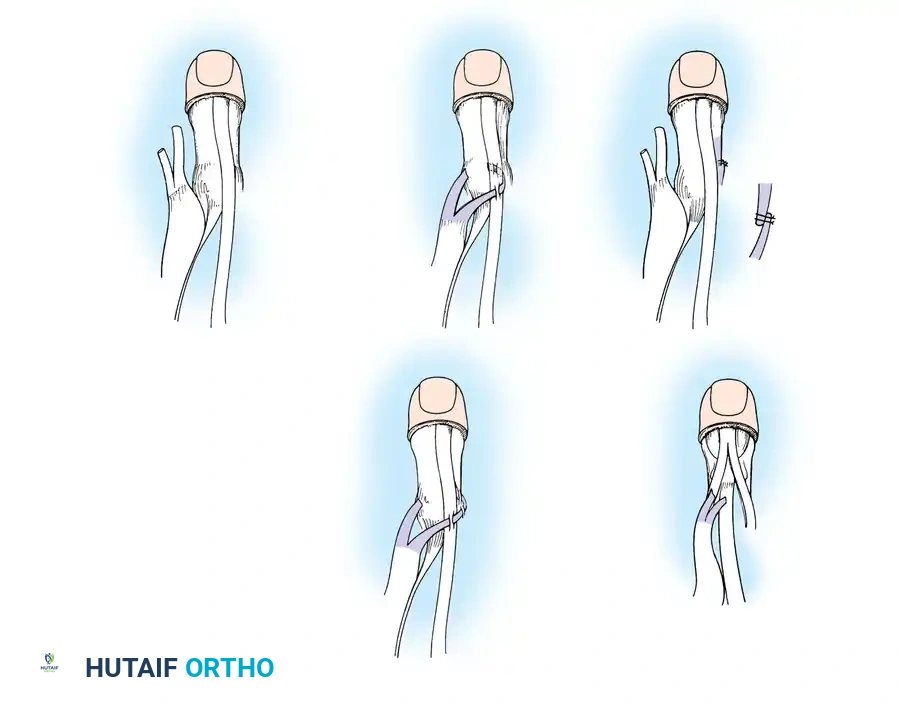

Surgical Interventions in Transverse Deficiencies

Surgical indications for transverse deficiencies are exceedingly rare. Epps, Burkhalter, and McCollough reported that out of 1,077 children